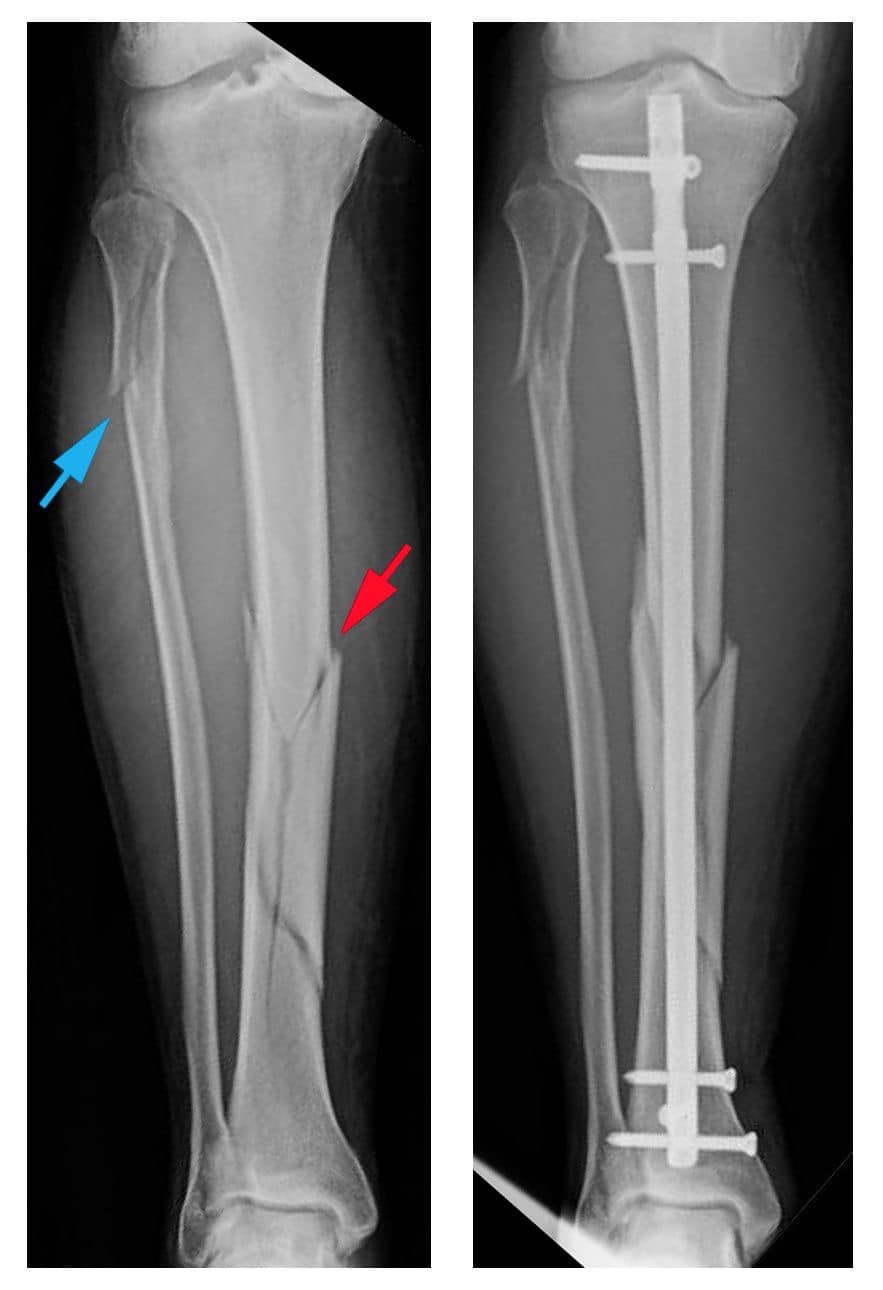

Khi nhập viện, đại diện BV Vạn Hạnh cho biết dù đau nhiều nhưng Hùng Dũng có sinh hiệu ổn định, các chỉ số mạch, huyết áp bình thường và tỉnh táo, tiếp xúc tốt. Kết quả chụp X-quang cho thấy bệnh nhân bị gãy xương mác và xương chày ở 1/3 giữa dưới cẳng chân khá nghiêm trọng.

Kiểu gãy: Kín, không có vết thương hở chảy máu, kiểu gãy ngang đơn giản

Cách điều trị: Mổ hở Kết Hợp Xương

- Kết hợp xương chày = nẹp vít (plate) hoặc đinh nội tuỷ có chốt (Intramedullary locking nail)

- Kết hợp xương mác = nẹp vít hoặc kim Kirschner

Nếu là đinh nội tuỷ: Không gây loãng xương dứoi nẹp, có thể để lâu hơn, có thể đau trước gối làm hạn chế chạy nhảy.